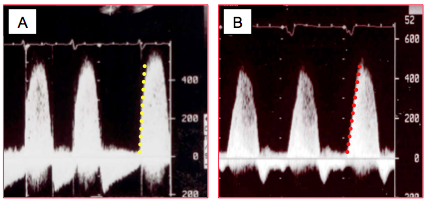

Figure 26.31 : Durée de l’IM vue en mode TM. A: IM protosystolique de courte durée apparaissant comme une simple flammèche (jet orange). B: IM pansystolique apparaissant comme un rideau.

Figure 26.33 : Image spectrale du flux Doppler d’une insuffisance mitrale. La trace dense et compacte traduit une IM sévère. A : fonction normale du VG, Vmax > 5 m/s et pente ascensionnelle très raide. B : fonction du VG diminuée, Vmax plus basse et pente plus faible.

Figure 26.34 : Flux Doppler spectral en cas d'IM (Doppler continu). A: IM sévère; la Vmax est 5-6 m/s, la trace est compacte et dense, l’enveloppe est bien définie et arrondie. B: IM sévère: le pic de vélocité est protosystolique mais la courbe est tronquée à cause de la POG élevée. C: flux Doppler d'une IM modérée; la trace est peu dense et l'enveloppe incertaine. D: le flux mitral démarre dès que la PVG dépasse 5-8 mmHg, bien avant l’ouverture de la valve aortique au moment de laquelle débute le flux artériel systémique; il n’y a donc pas de vraie phase isovolumétrique. Le flux aortique est plus triangulaire et sa durée est restreinte à la phase d'éjection.